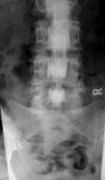

■ 脊髄腔造影

( ミエログラフィー )

脊髄造影検査とは、脊髄のくも膜下腔に造影剤を注入して脊髄、神経根の様子を調べる検査です。  脊髄神経は、背骨の後方の「脊柱管」という骨で囲まれた管の中を通っている細長いチューブのような組織で、周りを「硬膜」と「くも膜」という2枚の膜に包まれています。膜と脊髄の間(くも膜下腔)は「髄液」という液で満たされていて、脊髄神経はこの髄液の中で浮いている状態になっています。この髄液で満ちているくも膜下腔に造影剤を注入して、X 線写真で脊髄本体やそこから枝分かれして出ている神経の枝(神経根)の姿を映し出す検査がミエログラフィーです。 脊髄造影はMRI 検査よりも脊髄神経、神経根の外観を詳細に見ることができます。例えば椎間板ヘルニアがどの神経根をどのあたりで圧迫しているか、脊柱管がどれくらい狭くなっているかなどは MRI よりも分かりやすいです。またCT を同時に撮影して、造影された脊髄の横断面の様子を調べることもあります。